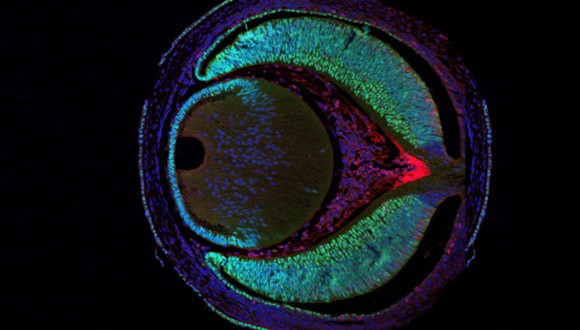

Cellular and Molecular Imaging Center

Our Imaging Center offers a wide variety of services, covering confocal and high-throughput microscopy, whole animal imaging and image analysis. All devices and instruments are centralized under one roof, providing a continuum of complete in-depth studies and projects in vivo and in vitro, from the micro to the macro level.

Whole animal imaging is monitored by Fluorescence and Bioluminescence Imaging, Fiber Confocal Microscopy, High sensitivity and High resolution Ultra-sound systems and a micro-CT scanner. Image analysis services include: Deconvolution and 3D and 4D Real-Time Interactive Image Visualization. We invite you to explore our website and find out more about the state-of-the-art facilities in our Imaging center.

The Histology core unit provides basic training and access to specialized high-quality instrumentation. Our services include sample preparation, paraffin blocks or frozen tissue processing, slide preparation and various staining technics (IHC, ISH and IF). We also provide H&E, Masson’s trichrome and PAS staining. Our staff can train the sample providers for independent use or provide full/partial service according to specific requirements.